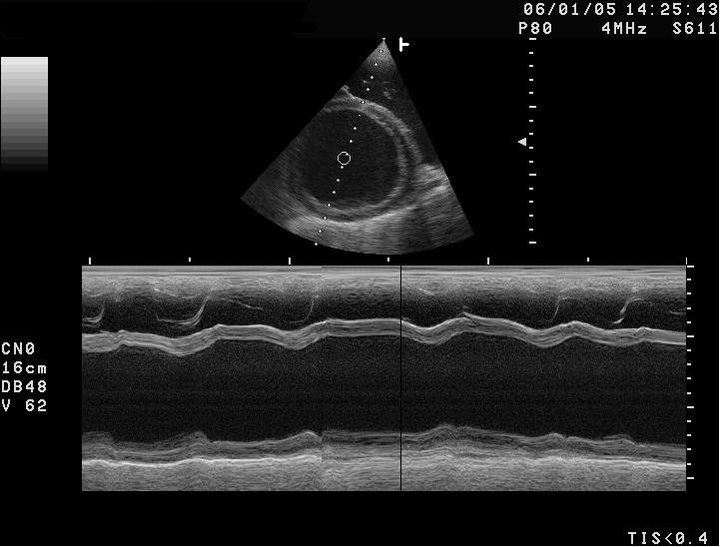

In the following M-mode USG, the X-axis represents _____ and the echo intensity is represented as brightness.

Flashcard 1 image

In the following _____-mode USG, the X-axis represents time and the echo intensity is represented as brightness.